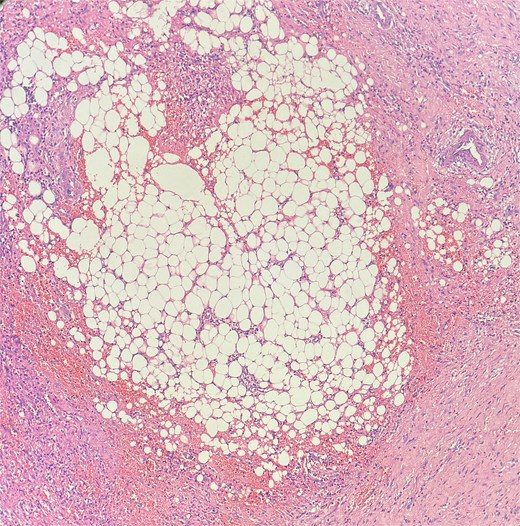

Picture depicting evidence of fat necrosis in the excised perianal tissue.

Sections show a dense inflammatory infiltrate within the subcutaneous adipose tissue, consistent with panniculitis. The infiltrate is composed of neutrophils, lymphocytes, plasma cells, and histiocytes.

Histopathological examination showed ghost-like adipocytes and foamy histiocytes.